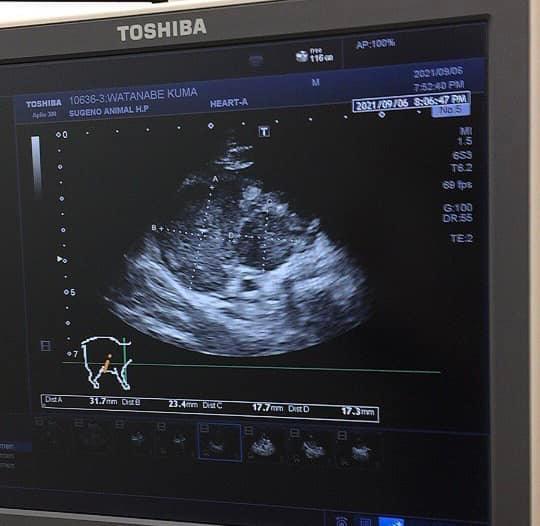

2021年9月6日に猫白血病ウイルスの発症により、縦隔型リンパ腫になっていることが判明。その後、抗がん剤治療に入ることとなりました。

発症の診断を受けた時のエコーには、胸腺に3個もの腫瘍ができており、胸水も溜まっていました。すぐに胸水を抜き、今後の治療法を聞かされました。